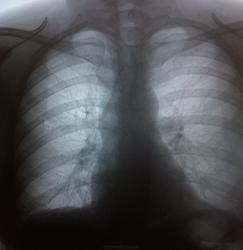

Пациентка, 41 г. Мед.осмотр. Есть ли изменения? И какая тактика?    25.04.14г.

Одну тенюшечку откопала, которой нет на архивных снимках. К фтизиатру напрашивается.

Мне кажется кальцинаты без особой динамики, а если правый корень смущает ( у меня тоже глаз зацепился), то досмотреть на Р-скопии. Вопрос: почему 25.04 и 6.05 -в чем разница ?

Я как-то ничего плохого не вижу.Левое поле лёгочное срезано.

А меня что-то левый корень смущает...

Странно... Я меня - что-то правый.)